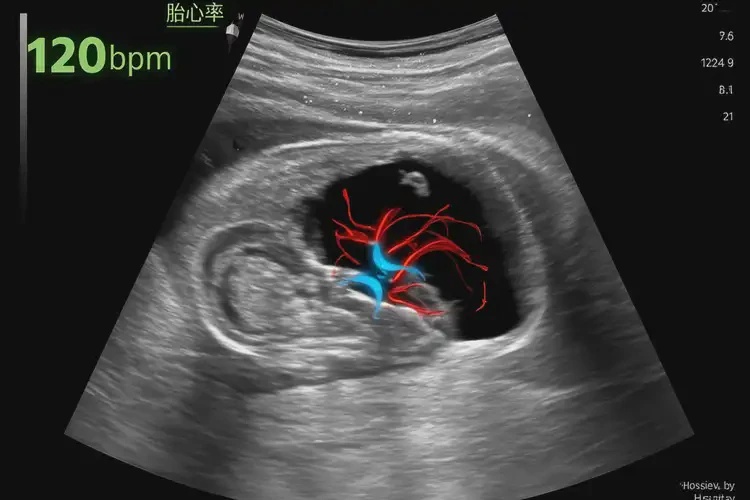

胎心88次/分鐘 在孕6周2天的情況下,可能屬于正常范圍,但也可能提示一些潛在問題。胎心率是指胎兒心臟每分鐘跳動(dòng)的次數(shù),通常在孕早期,胎心率會(huì)較快,大約在100-180次/分鐘之間。由于胎兒在孕早期較小,胎心率的測(cè)量可能會(huì)受到多種因素的影響,如胎兒的位置、母體的心率等。

1. 孕早期胎心率:在孕6周左右,胎兒的心臟已經(jīng)開始跳動(dòng),但此時(shí)胎心率可能會(huì)有較大的波動(dòng)。正常情況下,胎心率應(yīng)該在100-180次/分鐘之間。

孕6周2天胎心88怎么回事(圖1)